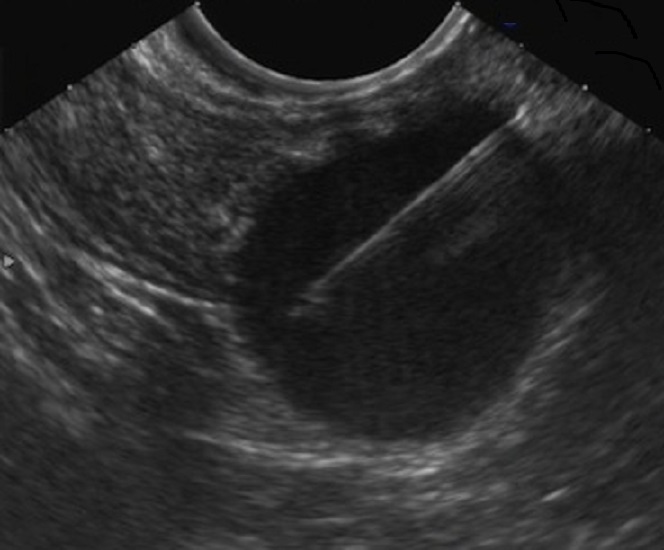

Echographie : Aspect

echographique lesionaire du cystadenome mucineuse du

pancreas est image du tumeur multiloculaire aechogen ou

hypoechogen , paroi epaisse > 2mm parfoi fin , a taille de

plus de > 10cm , forme par des petites kystes de moins < 2cm ,

parfois macrokystique , situe

dans le pancréas corporéo-caudal . N"a pas de

communication canalaire et lesion de calcification peripherique

parfois se en voyait